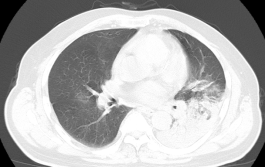

患者李先生,今年58岁,平时收购废弃钢材和塑料,10月27日因发热伴咳嗽、呼吸困难入住我院呼吸与危重症一科,入院时神志欠清,测体温39.4℃,血压87/56mmHg,末梢血糖26mmol/L。入院后,立即予完善相关检查,血气分析提示I型呼吸衰竭,胸部CT检查提示左肺大叶性肺炎伴实变,提示重症肺炎、感染性休克,种种迹象表明,患者病情危重,若不及时采取处理,随时可危及生命。